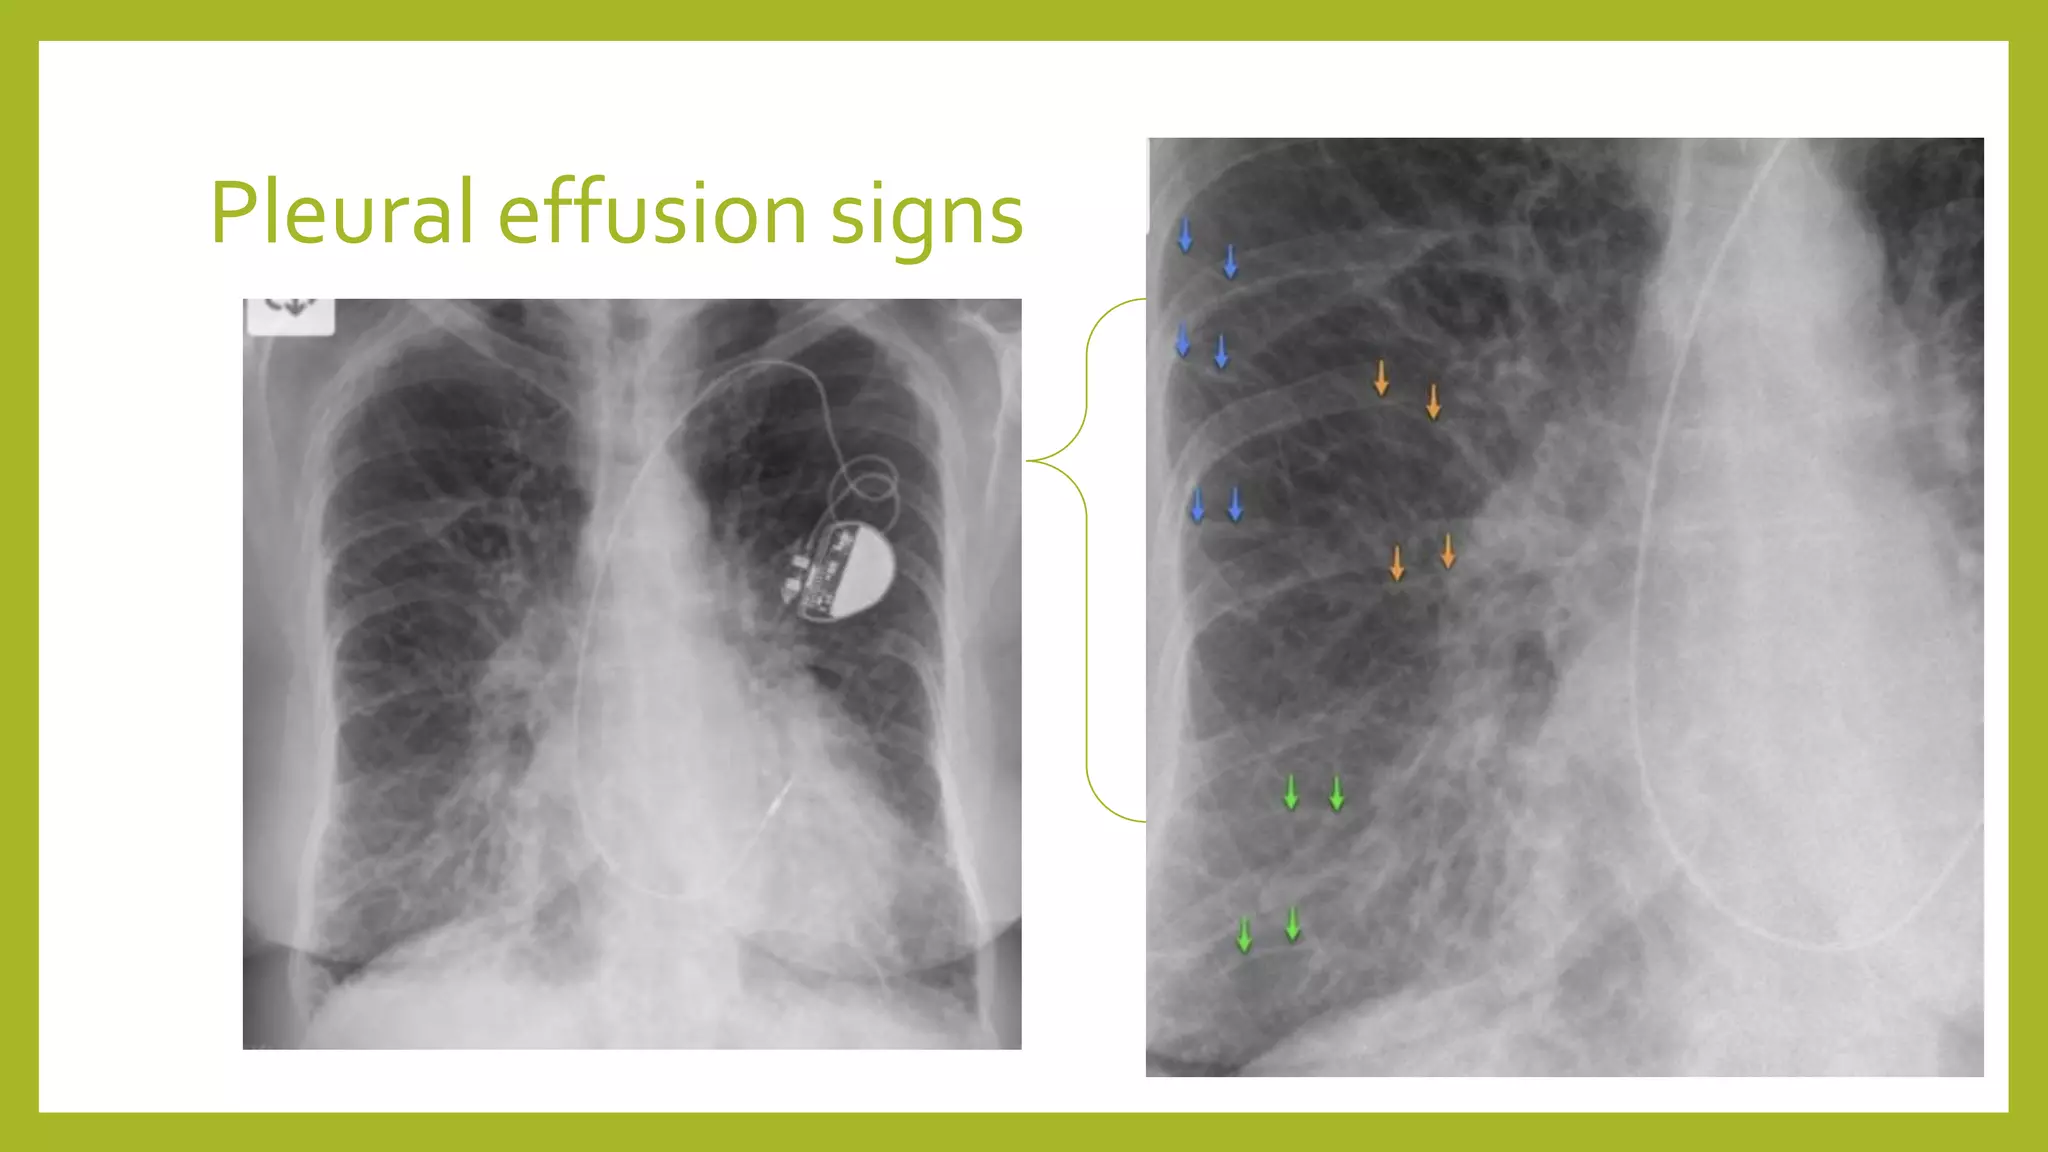

The document provides guidance on approaching and interpreting chest x-rays (CXR). It outlines steps to check the name, date and quality of the film, systematically scan the CXR looking for abnormalities, and determine if the lungs appear too white or black. Specific signs are described to help localize abnormalities, including the cardiac silhouette sign and pleural effusion signs. Examples are given of respiratory distress syndrome, tetralogy of fallot, transposition of great arteries, and total anomalous pulmonary venous return. The take home message is to summarize positive findings, compare to prior CXRs if available, and confirm findings with a radiologist.